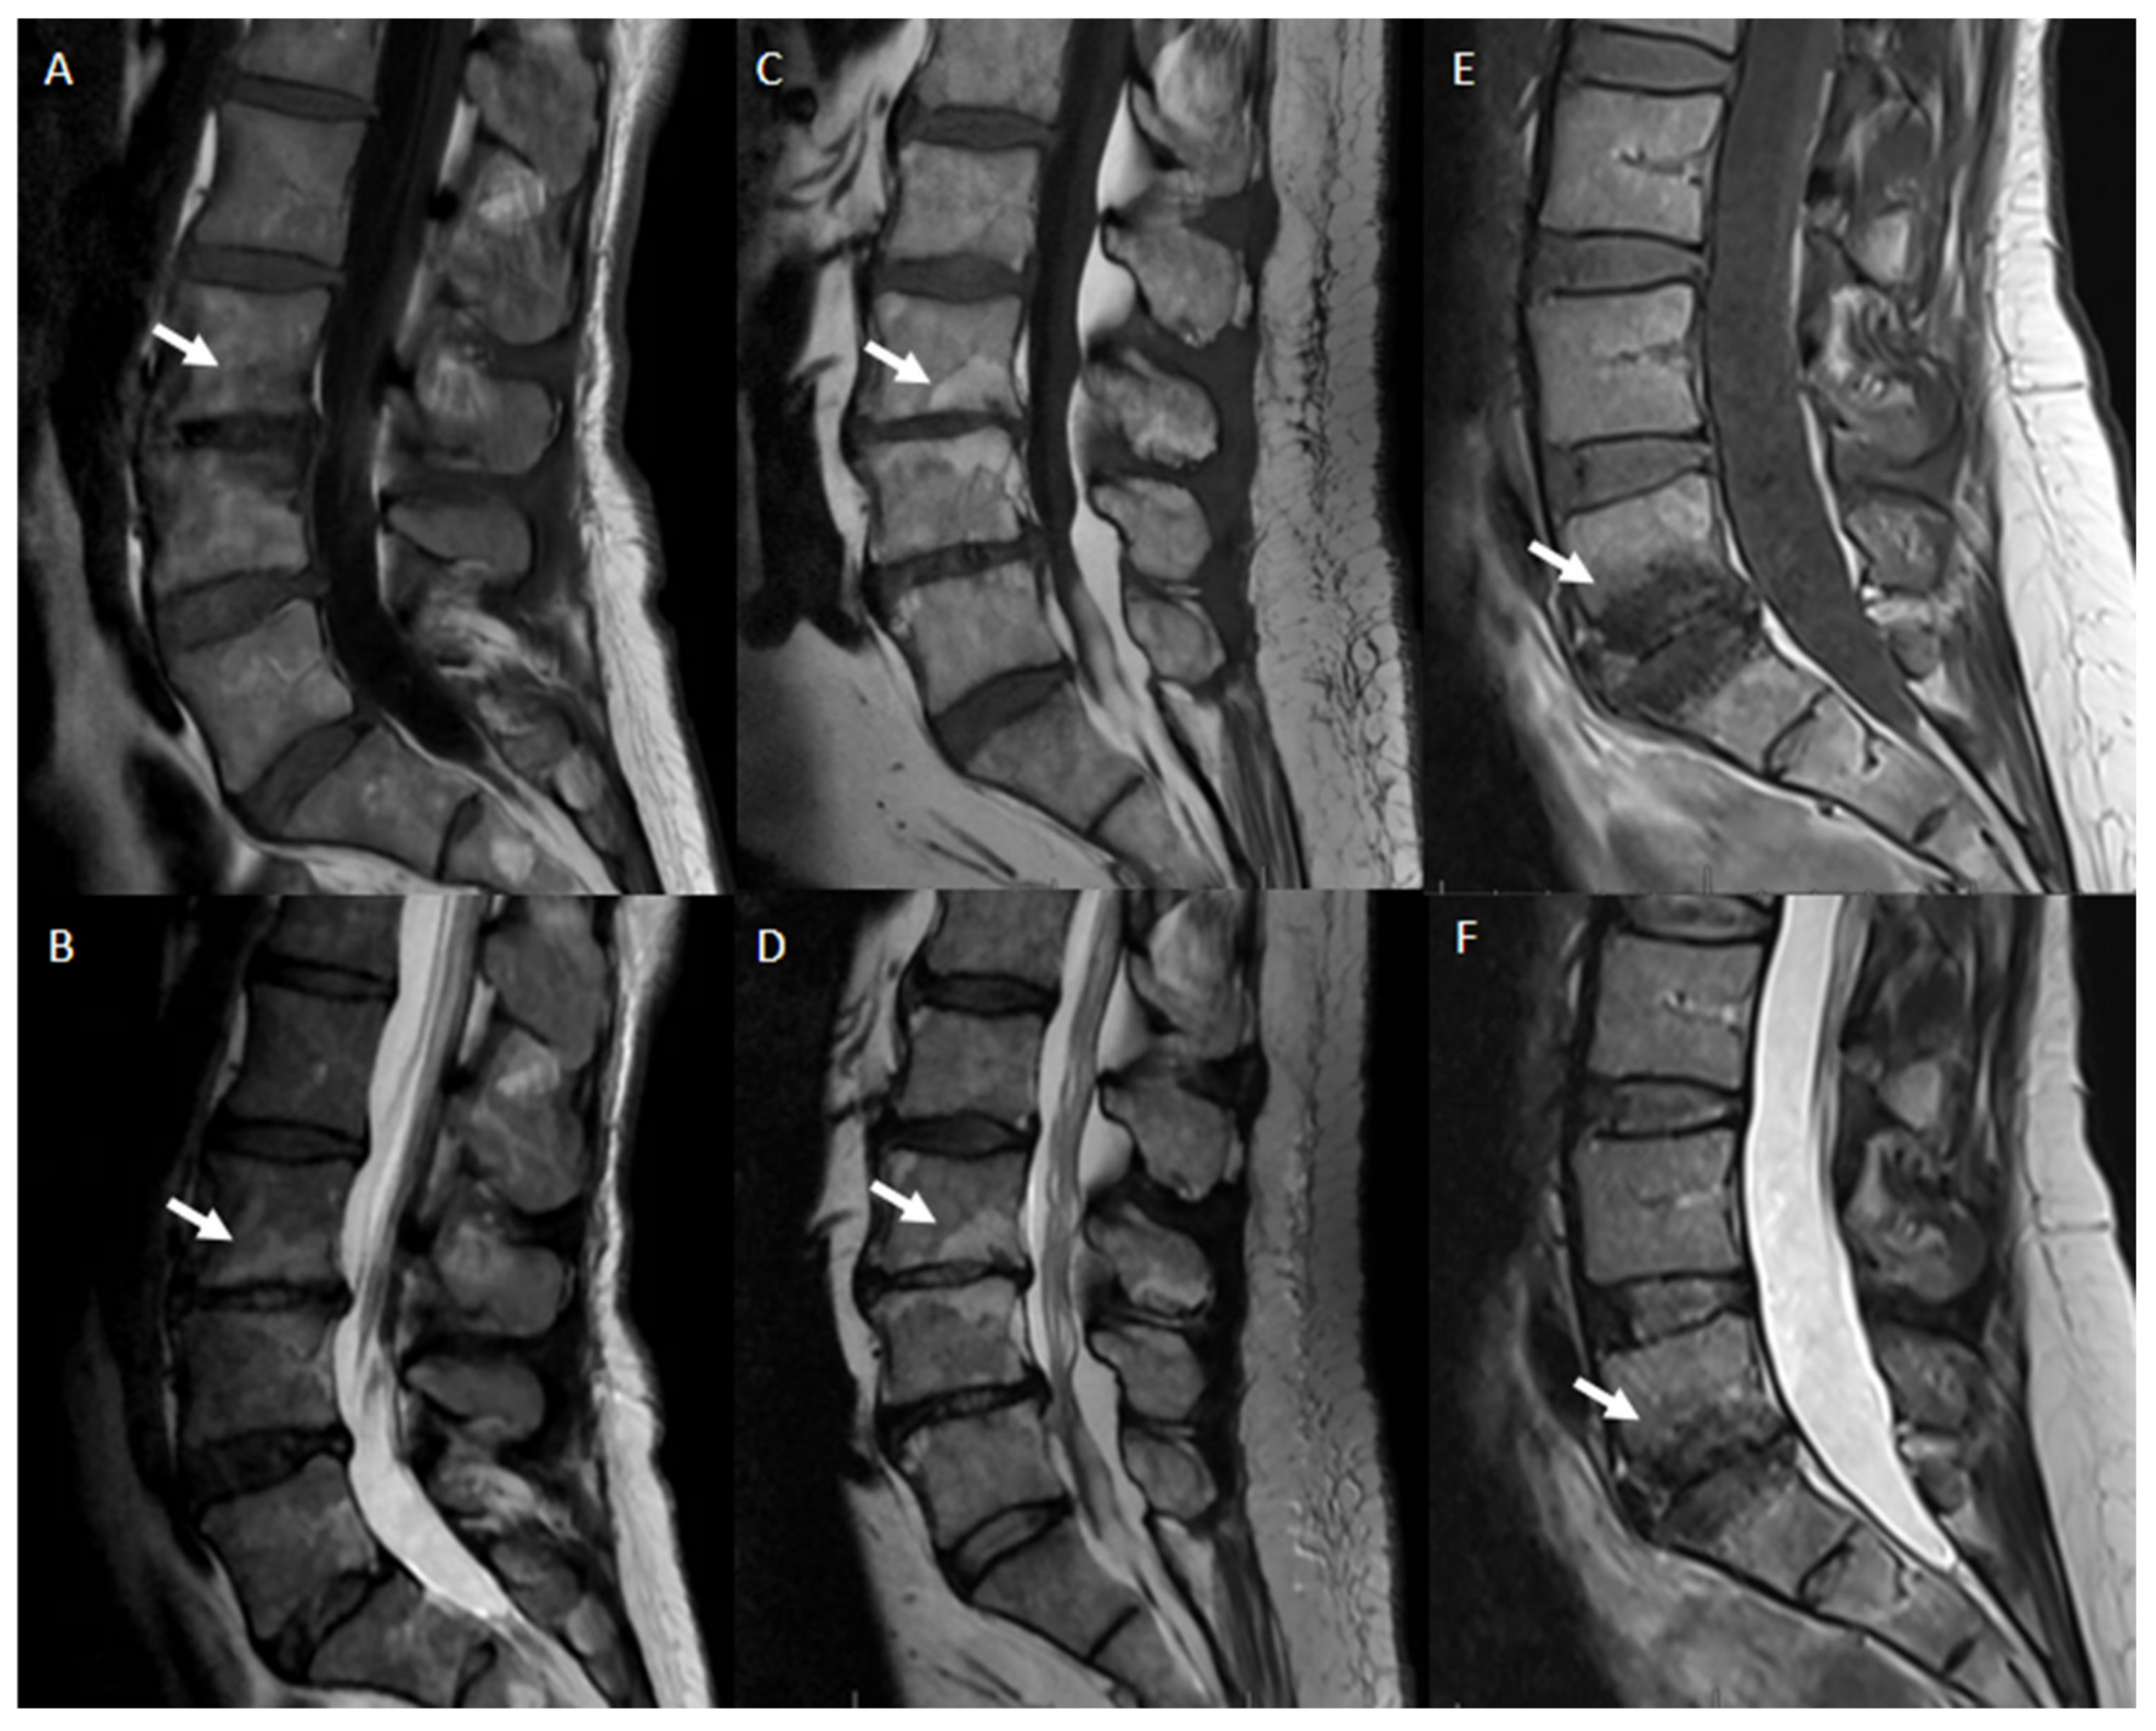

- Modic classification [16] is a classification for vertebral end plates and adjacent vertebral bodies MRI signal modifications secondary to disc inflammation and degenerative disc disease. Modic type 1 refers to decreased signal intensity on T1-weighted images and increased signal intensity on T2-weighted images. Such modifications may be chronic or acute and reflect the penetration of the end plate by fibrovascular tissue, inflammatory changes, and edema. Modic type II refers to increased signal intensity on T1-weighted images and isointense or increased signal intensity on T2-weighted images, indicating replacement of normal bone marrow by fat. Modic type III refers to decreased signal intensity on both T1- and T2-weighted images, indicating reactive osteosclerosis [55] (Figure 4).

Figure 4. Modic alterations, sagittal T1-weighted and T2-weighted MR images. Modic 1 (A,B): T1-hypointensity and T2-hyperintensity at L3–L4 representing bone edema (white arrows). Modic 2 (C,D): T1-hyperintensity and T2-hyperintensity at L3–L4 representing fat degeneration and red (haemopoietic) bone marrow conversion to yellow (fatty) bone marrow(white arrows). Modic 3 (E,F): T1-hypointensity and T2-hypointensity at L5–S1 representing subchondral bone sclerosis (white arrows).